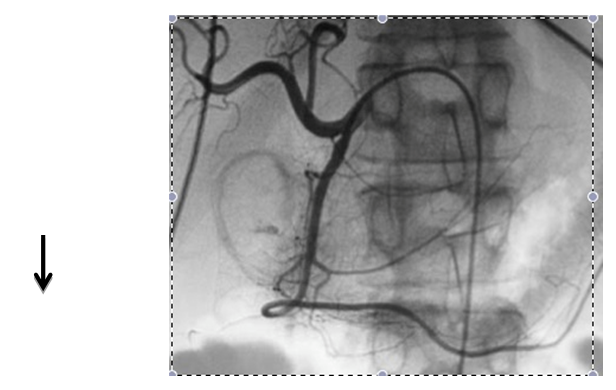

Embolization of upper gastrointestinal bleeding in oncological patients is commonly performed with a combination of agents: gelatin sponge (Gelfoan), coils, microcoils, and particles. These embolic agents function similarly to surgical ligation by decreasing perfusion pressure to the bleeding site; the reduction of blood flow promotes clot formation. Due to the dual blood supply of the stomach and duodenum, the risk of bowel ischemia is minimal when embolization is performed with coils and absorbable gelatin sponges. The catheter or microcatheter should be inserted into the selected artery in order to avoid deployment of embolic materials in undesired areas. This technique prevents ischemia or infarction, common complications of the procedure (Figure 1 & 2).

Figure 1 Embolization of the gastroduodenal artery in a patient with upper gastrointestinal bleeding. Common hepatic arteriogram shows a focus of extravasation in the region of the duodenum (arrow).